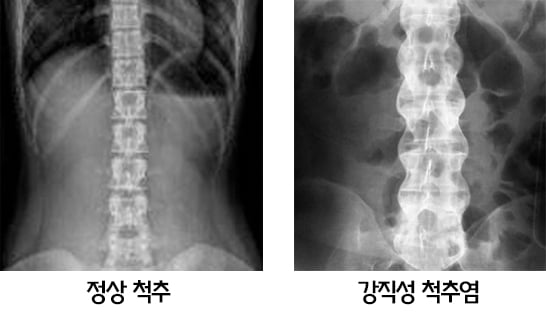

판단은 병원에서 피검사를 시행하면 HLA-B 27이라는 항목에 95% 정도이상이 양성 소견이 관찰되고 허리 와 고관절 CT, MRI검사를 통해서 확진 할수 있다. 주로 골반 뒤쪽에 위치하는 천장 관절에서 통증이 시작되며 종종 척추 이외에도 관절의 말단에 병이 침범하게 된다. 무릎이나 발목, 발뒤꿈치의 아킬레스건 통증이 동반되는 경우도 있다. 전신적인 질환이기 때문에 눈에 포도막염이 생겨서 충혈이 되는 경우도 있다. 병이 진행이 되면 척추 관절이 굳어서 목과 허리가 앞으로 휘

게 되는데 사진상에서도 척추의 마디 마디가 분리 되어있지 않고 연결되어 마치 대나무처럼 보이게 된다. 치료는 약물치료 와 근골격계에 대한 재활 치료를 같이 병행 해야 하는데 주로 쓰는 약제는 일차적으로 소염제를 사용 한다. 만약 병이 진행 되는 경우는 이차적으로 류마티스에 쓰는 약제를 추가 해서 사용하고 심하면 생화학 제제를 사용을 하고 있다.